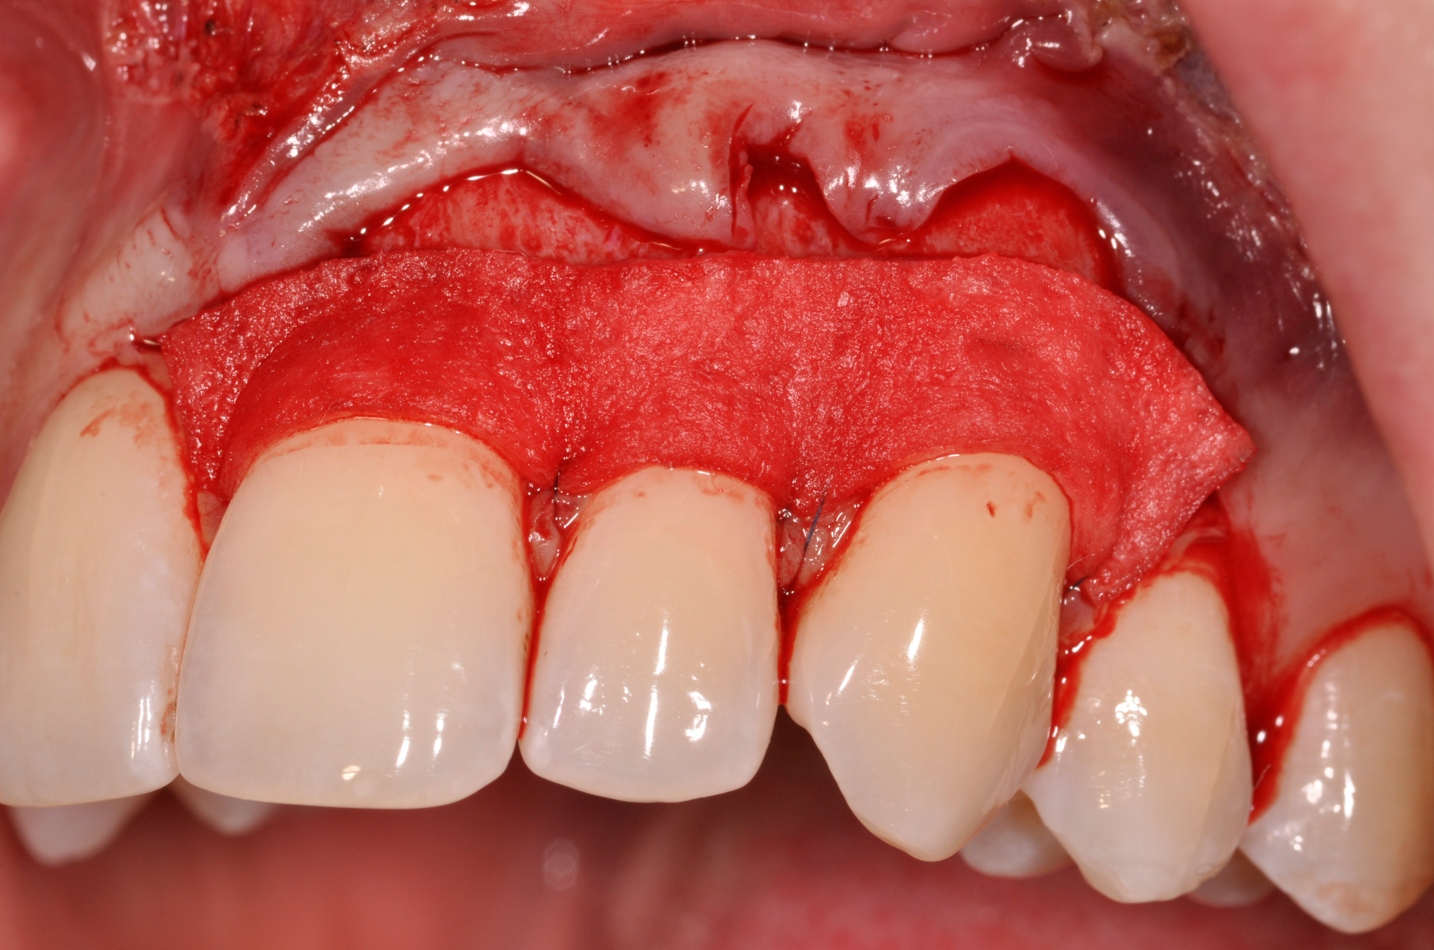

The authors have introduced a laser-assisted vestibuloplasty approach (LAVA) procedure that is designed to prevent recurrent recession after surgical correction, which has been reported in the literature.29,38 This first involves a flap procedure for insertion of the dermal matrix graft material to be used to achieve root coverage and increase zones of existing attached keratinized tissues. To complete the vestibuloplasty procedure, the surgeon separates the mucosal tissues apical to the preexisting mucogingival junction in the area of the teeth exhibiting gingival recession. The authors advocate using a Nd:Yag laser with a power setting at 5 watts to accomplish the vestibuloplasty and release any excessive muscle attachments or frenal pulls in the affected areas (Figure 3).

The flap approach follows an incision design where the crest of the papilla is preserved and a V-type incision is made in the papillary tissues (Figure 4). This allows the preexisting papillary tissues in the area just inferior to the contact point of the natural teeth affected to be used as a tissue bed to provide vascularization to the flap/dermis complex. Prior to securing the dermal matrix tissue, the papillary tissues that remain after the incision technique outlined must be de-keratinized by using a #4 round diamond bur. This allows for the introduction of initial blood flow and vascularization of the dermal matrix tissues and nourishment of the coronally repositioned flap in the critical area of the interproximal papillary tissues. After securing the dermal matrix tissue from the palatal/lingual aspect of the teeth being treated and coronally repositioning the buccal flap, closure is achieved using an interrupted sling suturing technique.

A 24-year-old, nonsmoking man presented for correction of gingival clefting and recession in the maxillary left anterior sextant (Figure 6). The patient’s medical history was noncontributory. After consultation and presenting various options to the patient to correct the localized recession, the patient opted for the use of acellular dermal matrix tissue rather than harvesting tissue from his palatal area.

After administration of an appropriate local anesthetic, a laser-assisted split-thickness vestibuloplasty was performed superior to the mucogingival junction from the right central incisor to the left first premolar region (Figure 7). Prior to any incisions being performed, a 20-mm x 40-mm dermal matrix graft (Puros Dermis), a 0.8-mm to 1.7-mm thick piece of tissue, was trimmed to appropriate length and width to correct the gingival defect present (Figure 8). The tissue graft was sized to 6 mm in height and spanned to the mesial line angle of the left central incisor to the distal line angle of the left canine area. The dermal matrix graft was rehydrated with the patient’s own platelet-rich plasma solution, which was harvested from 20 cc of whole blood collected immediately prior to the surgical procedure (Figure 9).

After initial incision techniques were done, a papillary-sparing incision was performed, leaving the crest of the papilla intact (Figure 10), thus allowing flap closure to be accomplished with a bed of autogenous tissue to support revascularization of the dermis/buccal flap complex. A full-thickness flap was then elevated to the mucogingival junction, after which a split-thickness dissection with a blunt elevator superior to the mucogingival junction area was performed to allow for release of tension and to let the buccal flap be mobilized coronally at closure (Figure 10). Care must be taken to avoid perforating the tissue in the region of the vestibuloplasty incision. After tension-free release of the flap, root planing of the exposed root surfaces was accomplished, followed by removal of the smear layer of cementum and chemical detoxification with a citric acid solution pH1 applied over the previously root-planed surfaces. After root preparation, the keratinized papillary tissues that remained following initial incisions were de-keratinized by using a #4 round diamond on a high-speed handpiece. De-keratinization provided a wound bed that enabled the dermal matrix graft to be secured and supported revascularization of the coronally repositioned buccal flap at closure.

Fig 3. Example of laser-assisted split-thickness

vestibuloplasty.

Figure 3

Fig 7. Laser-assisted split-thickness vestibuloplasty performed.